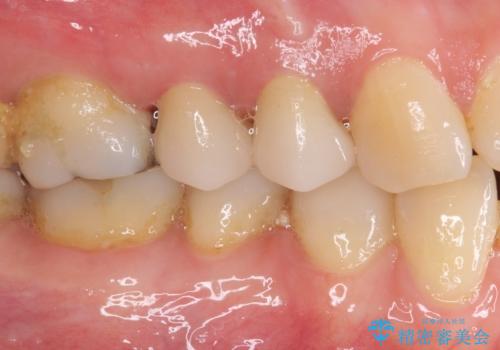

根管治療を行った後に、ガラス系セラミッククラウンにて補綴することとしました。

透明感のある自然な仕上がりとなり、患者様には大変満足していただきました。